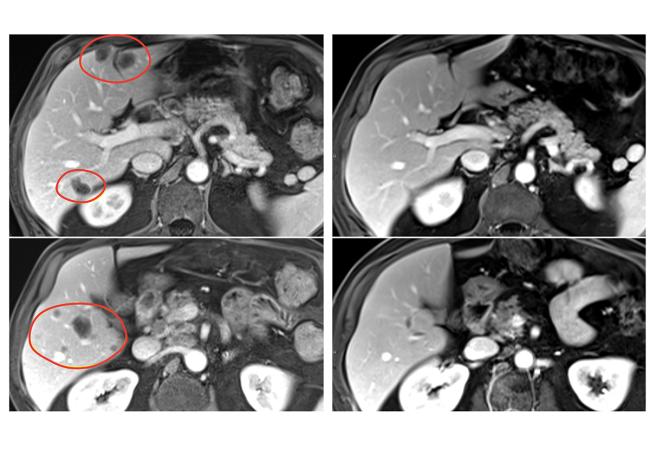

Patients in the clinical trial, who had a variety of gastrointestinal tumors, also received the immune checkpoint inhibitor pembrolizumab (Keytruda) to help further boost their immune response. The result was nearly 24% of patients treated with selected TILs plus pembrolizumab had a substantial reduction in the size of their tumors, compared with 7.7% of patients who received selected TILs without pembrolizumab. Patients treated with TILs that had not been selected for anti-tumor activity had no tumor shrinkage.

The clinical trial included 91 patients with metastatic gastrointestinal cancers—including esophageal, stomach, pancreatic, colon, and rectal cancers—that had worsened despite a median of four prior treatment regimens. In the pilot phase of the trial, 18 patients were treated with TILs that had not been selected for anti-tumor activity, and there were no objective responses (tumor shrinkage of at least 30% is considered an objective response). In the second phase, 39 patients were treated with selected TIL therapy, and three (7.7%) had objective responses.

In the third phase, 34 patients received pembrolizumab immediately before selected TIL therapy to prevent the newly introduced immune cells from becoming inactivated by the patient’s own immune system. This group had the best response, with 8 of 34 (23.5%) patients experiencing an objective response. All 91 patients had also received standard chemotherapy and high-dose interleukin-2 before the TIL therapy.

In the trial’s second and third phases, objective responses were seen in multiple types of gastrointestinal cancers, including cancers of the colon, rectum, pancreas, and bile duct. Responses lasted between 8 months and more than 5.8 years in the group that received selected TIL therapy alone, and between 4 months and 3.5 years in the group that received selected TIL therapy and pembrolizumab. Serious side effects occurred in 30% of patients treated with selected TILs.